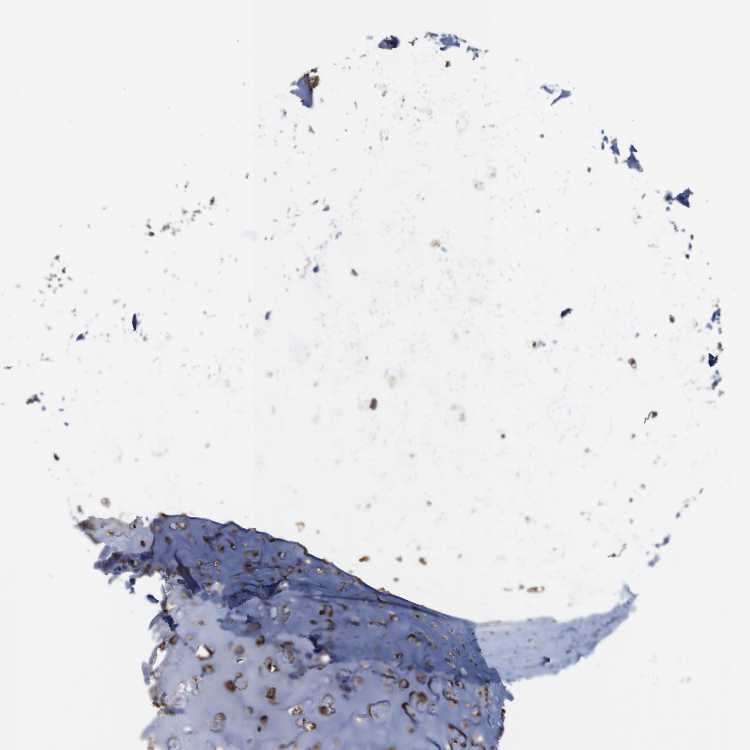

ADIPOSE TISSUE - Antibody stainingi

Antibody staining in the annotated cell types in the current human tissue is reported as not detected, low, medium, or high, based on conventional immunohistochemistry profiling in selected tissues. This score is based on the combination of the staining intensity and fraction of stained cells.

Each image is clickable and will lead to virtual microscopy that enables deeper exploration of all samples and also displays staining intensity scores, fraction scores and subcellular localization as well as patient and tissue information for each sample.

Antibody HPA014906

Adipocytes High